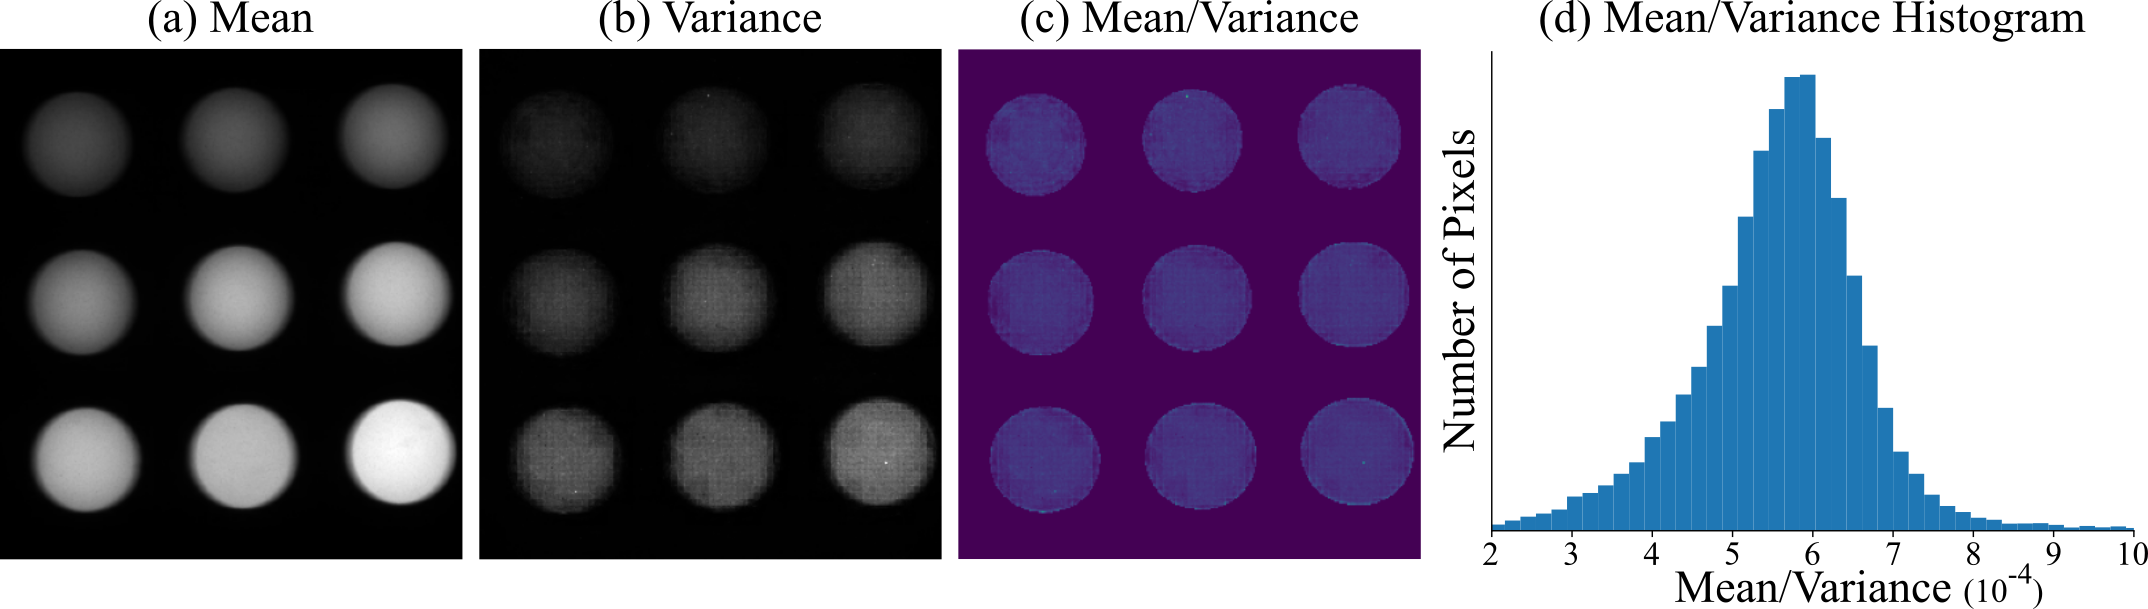

Figure 1: Gain Calibration Images: This figure shows the (a) mean, (b) variance, and (c) the mean divided by the variance of the Quel calibration phantom from OL-Phantom used to calibrate for our K𝐾K parameter. (d) shows the histogram of mean divided by variance values for the 9 wells. The mean value of this histogram is our calibrated K𝐾K value. Notice that the mean divided by variance values are similar in all wells indicating that a Poisson distribution is correct for the brightness level of this phantom.

I-A Gain (K)

In order to solve for the K𝐾K in our noise generation model in Eq. 1, we do the following calibration procedure. First, we capture a video with 1,830 frames of the Quel calibration phantom [13] (OL-Phantom). The Quel phantom contains 9 wells of varying ICG mimicking fluorescence concentrations. We then take the mean and variance of each pixel across time. We then assume that the Poisson noise term dominates (i.e. read noise is negligible) so our measurements, I𝐼I, will be Poisson random variables with mean equal to variance. Therefore, K𝐾K can be estimated as,

I𝐼\displaystyle I =KPois(S)absent𝐾Pois𝑆\displaystyle=K\text{Pois}(S) (1)

Var[I]Vardelimited-[]𝐼\displaystyle\text{Var}[I] =K2Sabsentsuperscript𝐾2𝑆\displaystyle=K^{2}S (2)

E[I]Edelimited-[]𝐼\displaystyle\text{E}[I] =KSabsent𝐾𝑆\displaystyle=KS (3)

K𝐾\displaystyle K =Var[I]E[I]absentVardelimited-[]𝐼Edelimited-[]𝐼\displaystyle=\frac{\text{Var}[I]}{\text{E}[I]} (4)

where E is the expectation across time, and Var is the variance across time. We use Eq. 4 to estimate a K𝐾K value for each pixel in a Quel phantom well, we average the estimates to give a final estimate of K=11764𝐾11764K=\frac{1}{1764} when I𝐼I is scaled between 0 and 1.